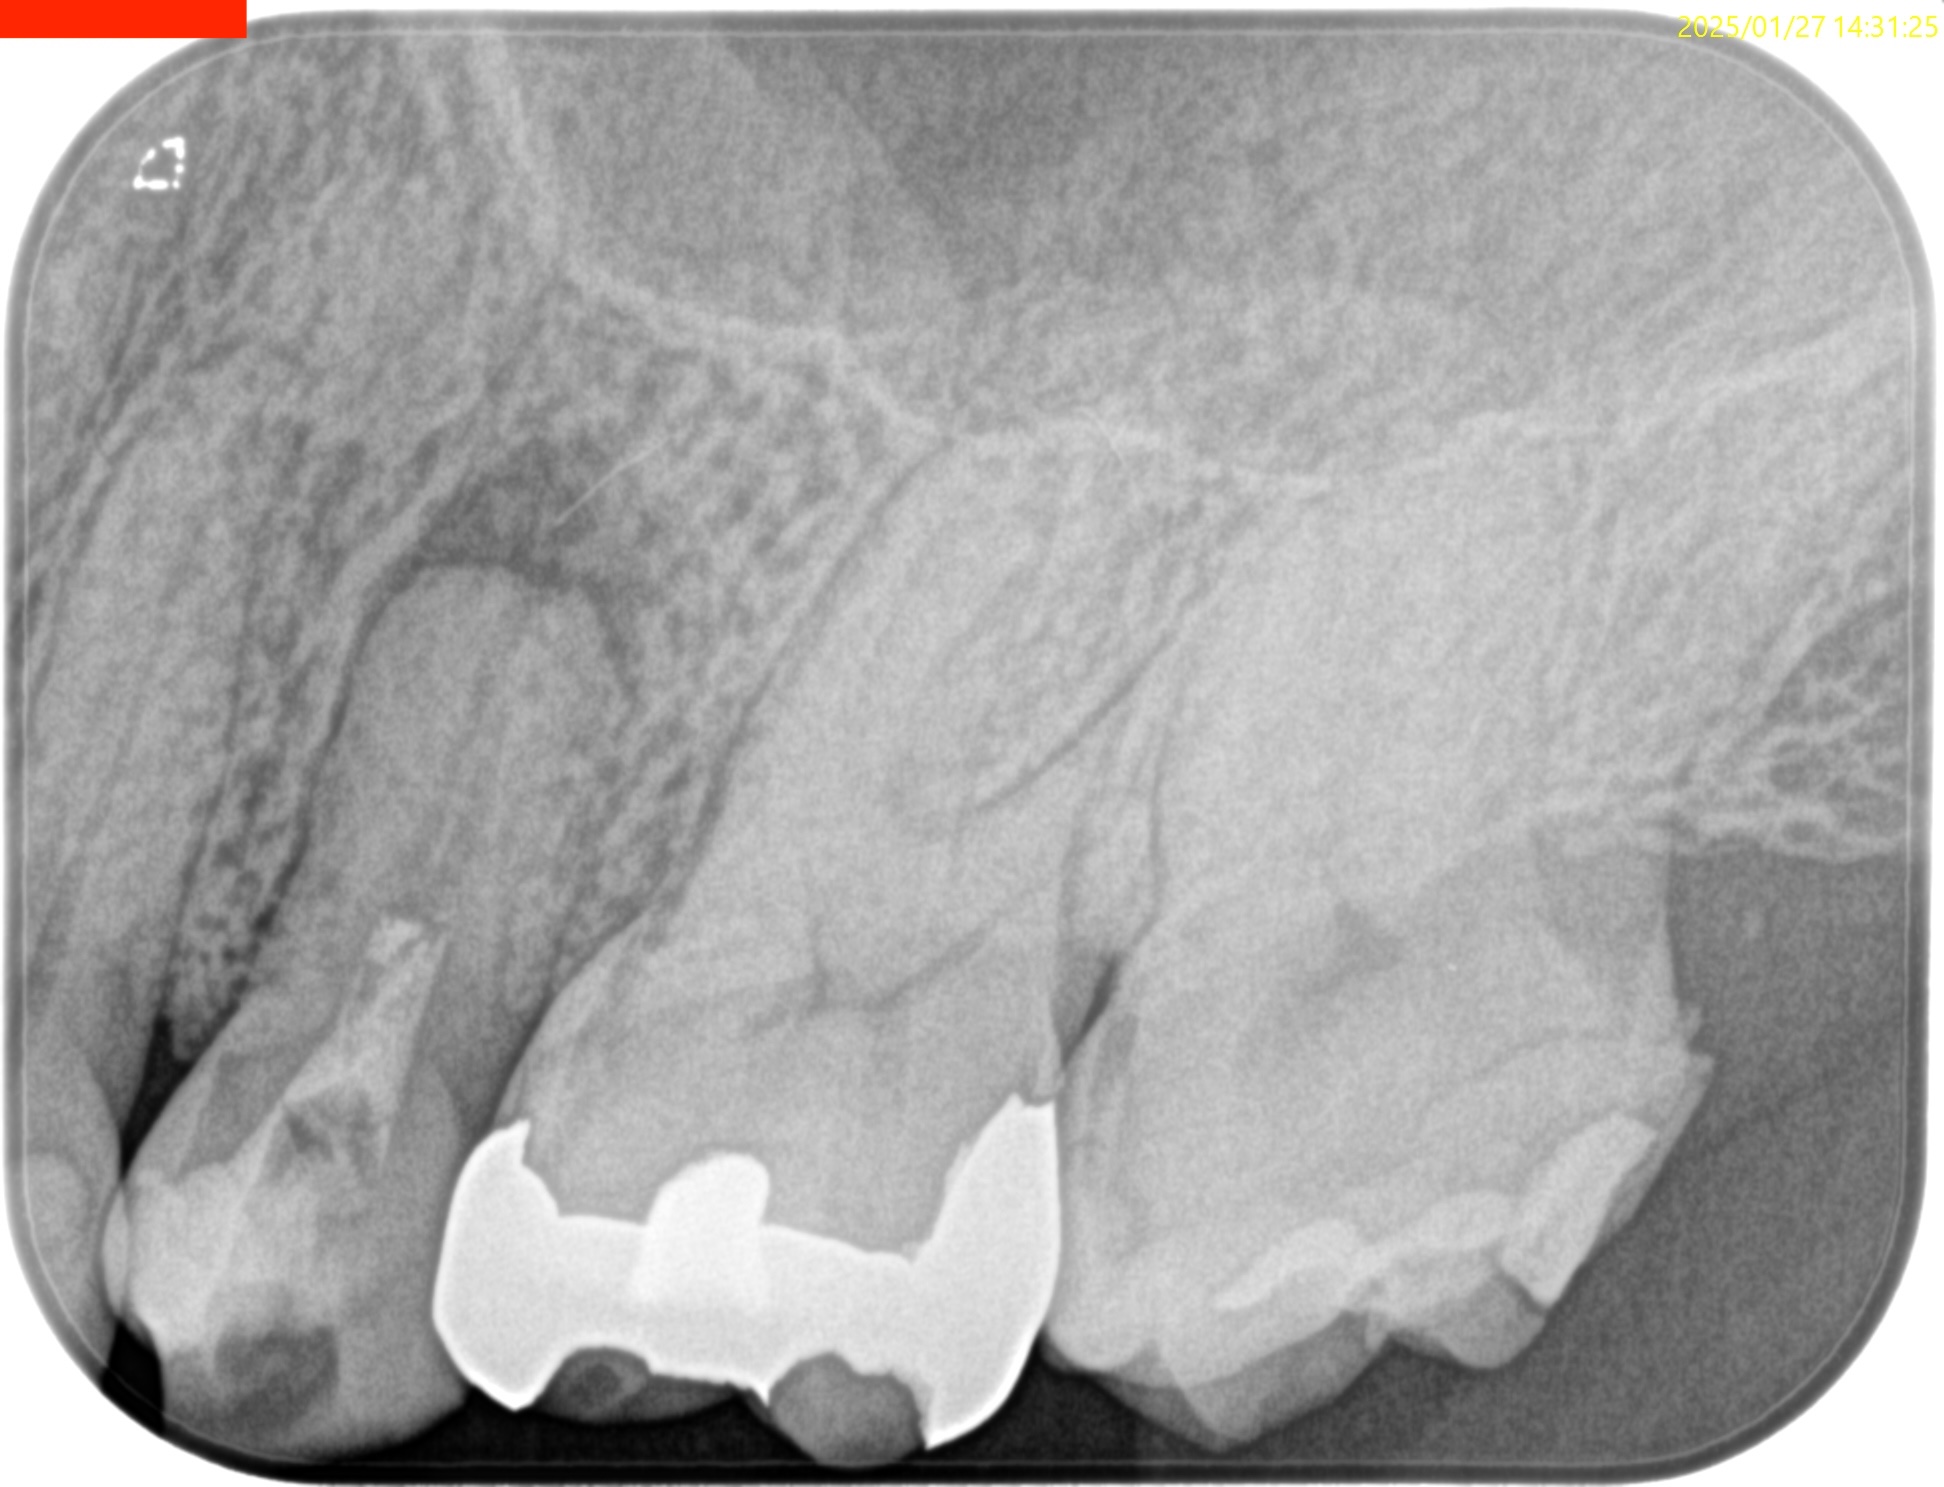

またCBCTを撮影すると、

歯槽骨は溶けて#13のApexが口腔内に露出しかけている。

これが圧痛の原因になるのは間違いないだろう。